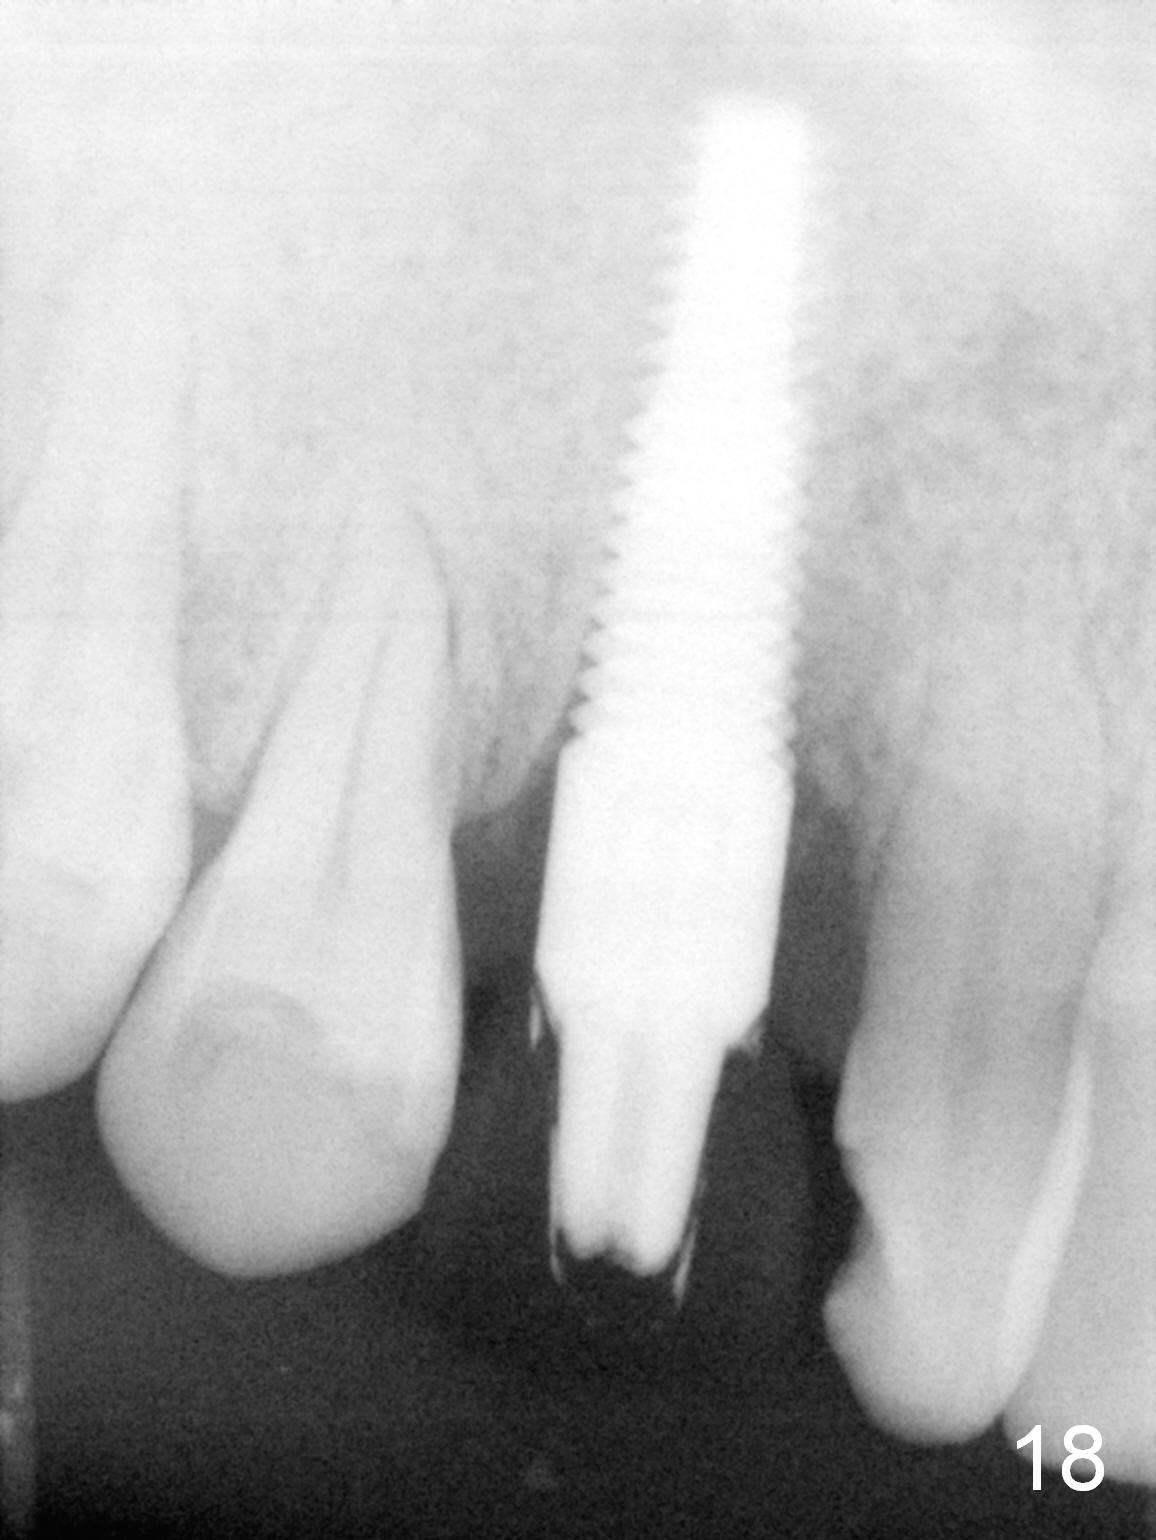

One and a half months later (3 months postop), the patient returns for final crown impression. The buccal gingiva has grown coronally (Fig.17 arrow). The implant appears to have osteointegrated (Fig.18). The buccal plate has become concave (Fig.19 arrowheads). To maintain the gingival level, the buccal portion of the implant/abutment (Fig.19 *) is going to be reduced (Fig.20 *). The margin of the definitive restoration will be at the prep margin and thin so that the gingiva is expected to continue to be growing coronally after cementation.